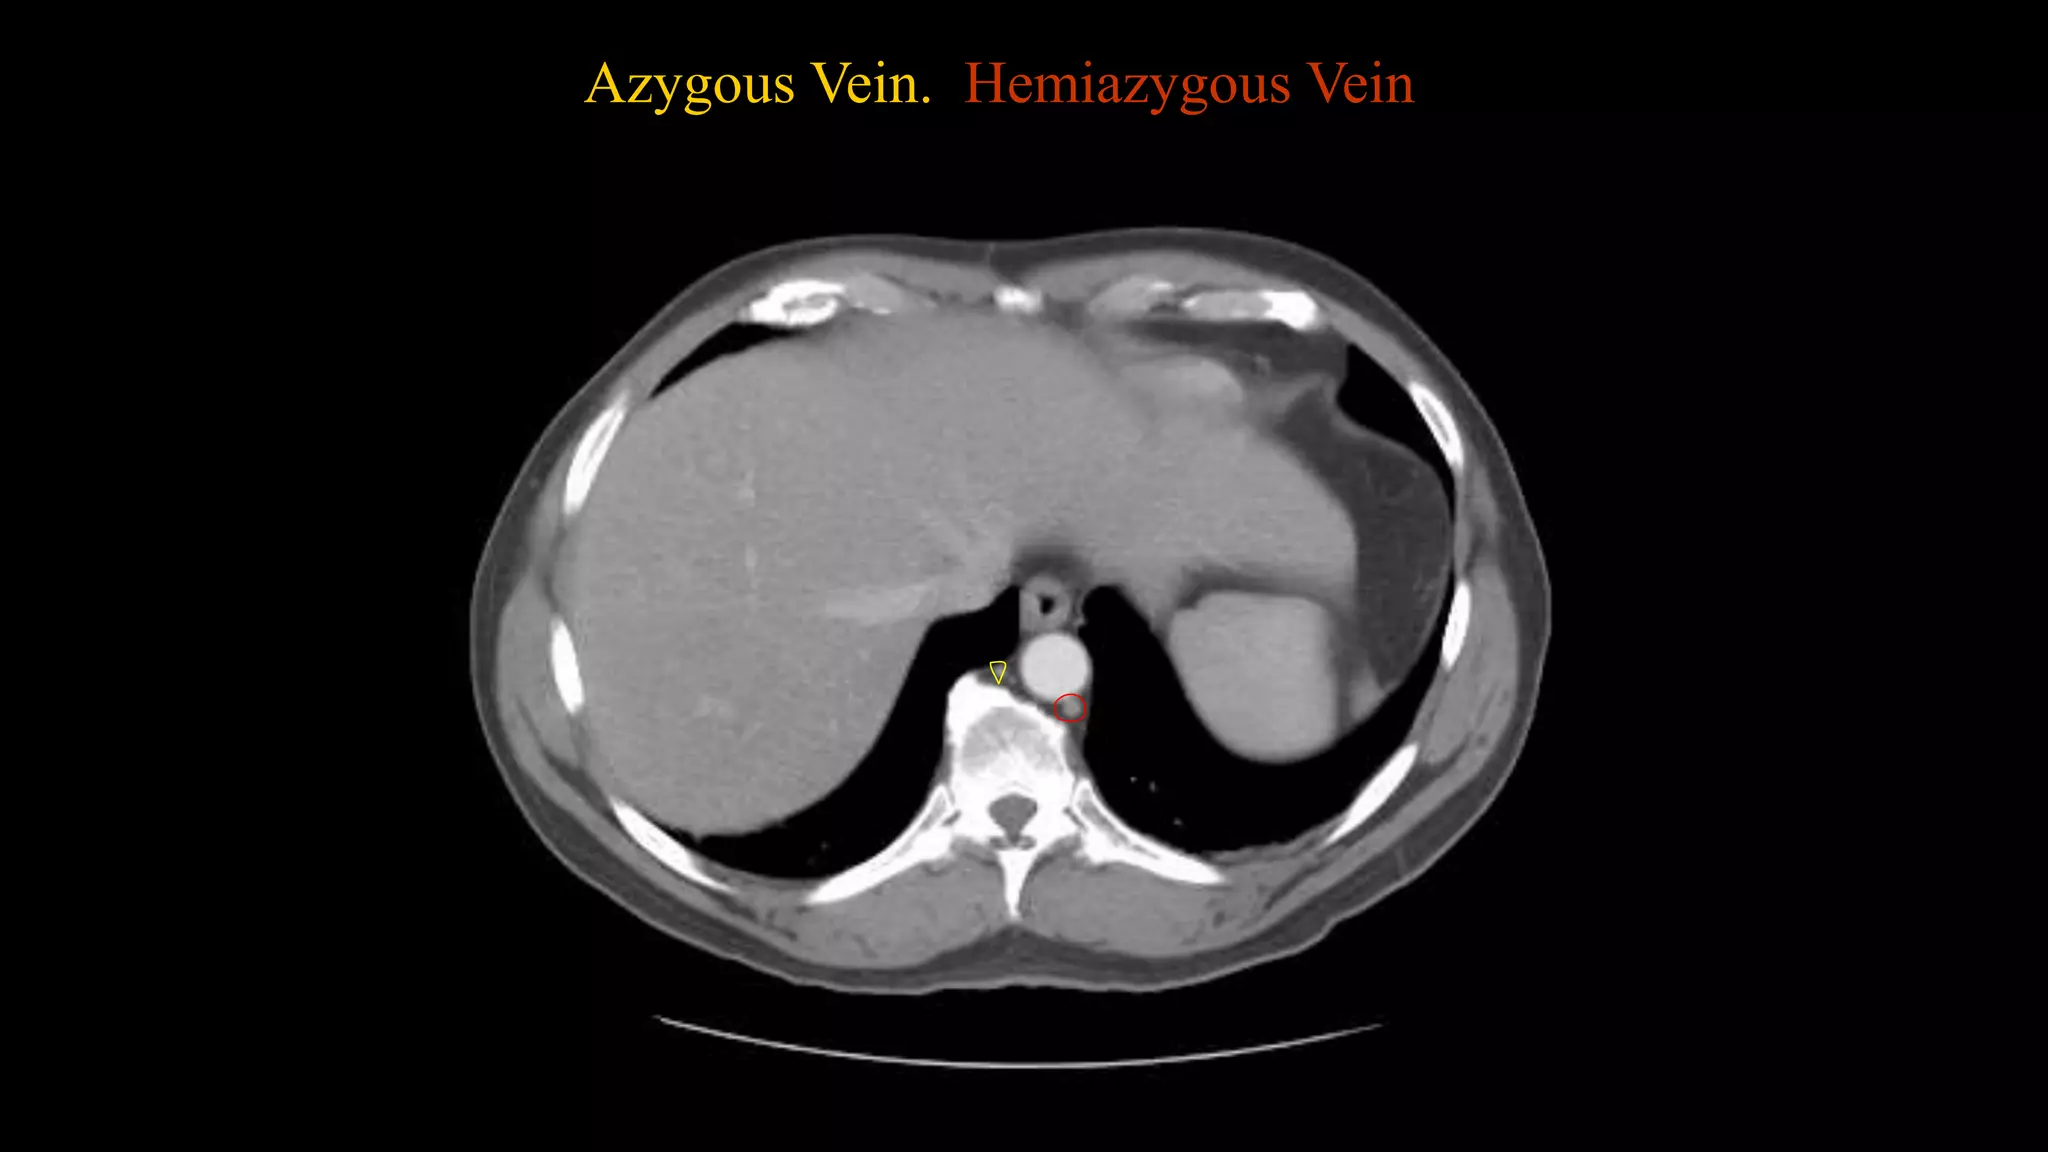

 In this sequence of images, we will label the abdominal vasculature.

The CT images are 5mm slices with soft tissue window settings. IV

labels to assist with tracking the vessels.

Azygous Vein. Hemiazygous Vein

Studying the CTimage  In this sequence of images, we will label the abdominal vasculature. The CT images are 5mm slices with soft tissue window settings. IV and oral contrast have been administered which causes the vessels and GI tract to appear hyperdense (white). Some images will contain labels to assist with tracking the vessels.  IMAGES ARE VIEWED AS LOOKING FROM THE FEET RIGHT LEFT

Follow the IVcontrast filled Aorta as we descend caudally. Branches and points of interest will be noted.